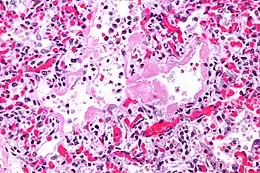

_Idiopathic_DAD_2.jpg)

_Idiopathic_DAD.jpg)